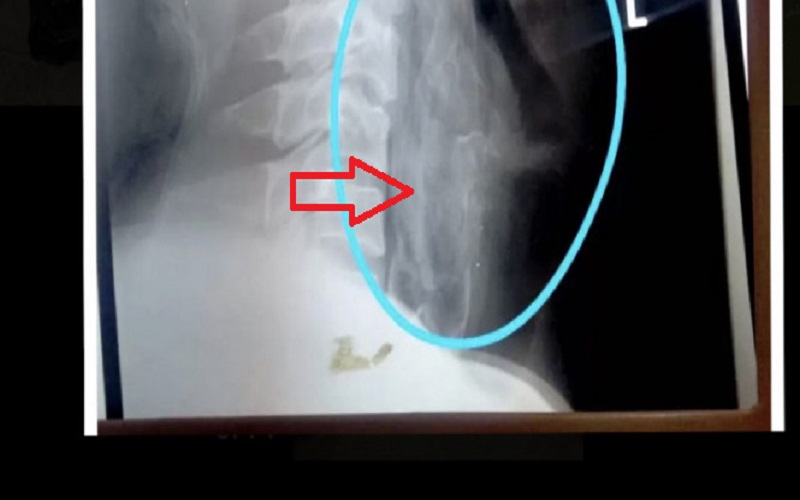

Hasil rontgen pasien yang tenggorokannya tersangkut ikan Papuyu (Foto: Antaranews Kalsel/Ragil Darmawan)

Selanjutnya, pihaknya melakukan rontgen terhadap pasien tersebut. Ternyata ikan itu cukup besar dan duri-durinya sudah menyangkut di dinding tenggorokan pasien tersebut.